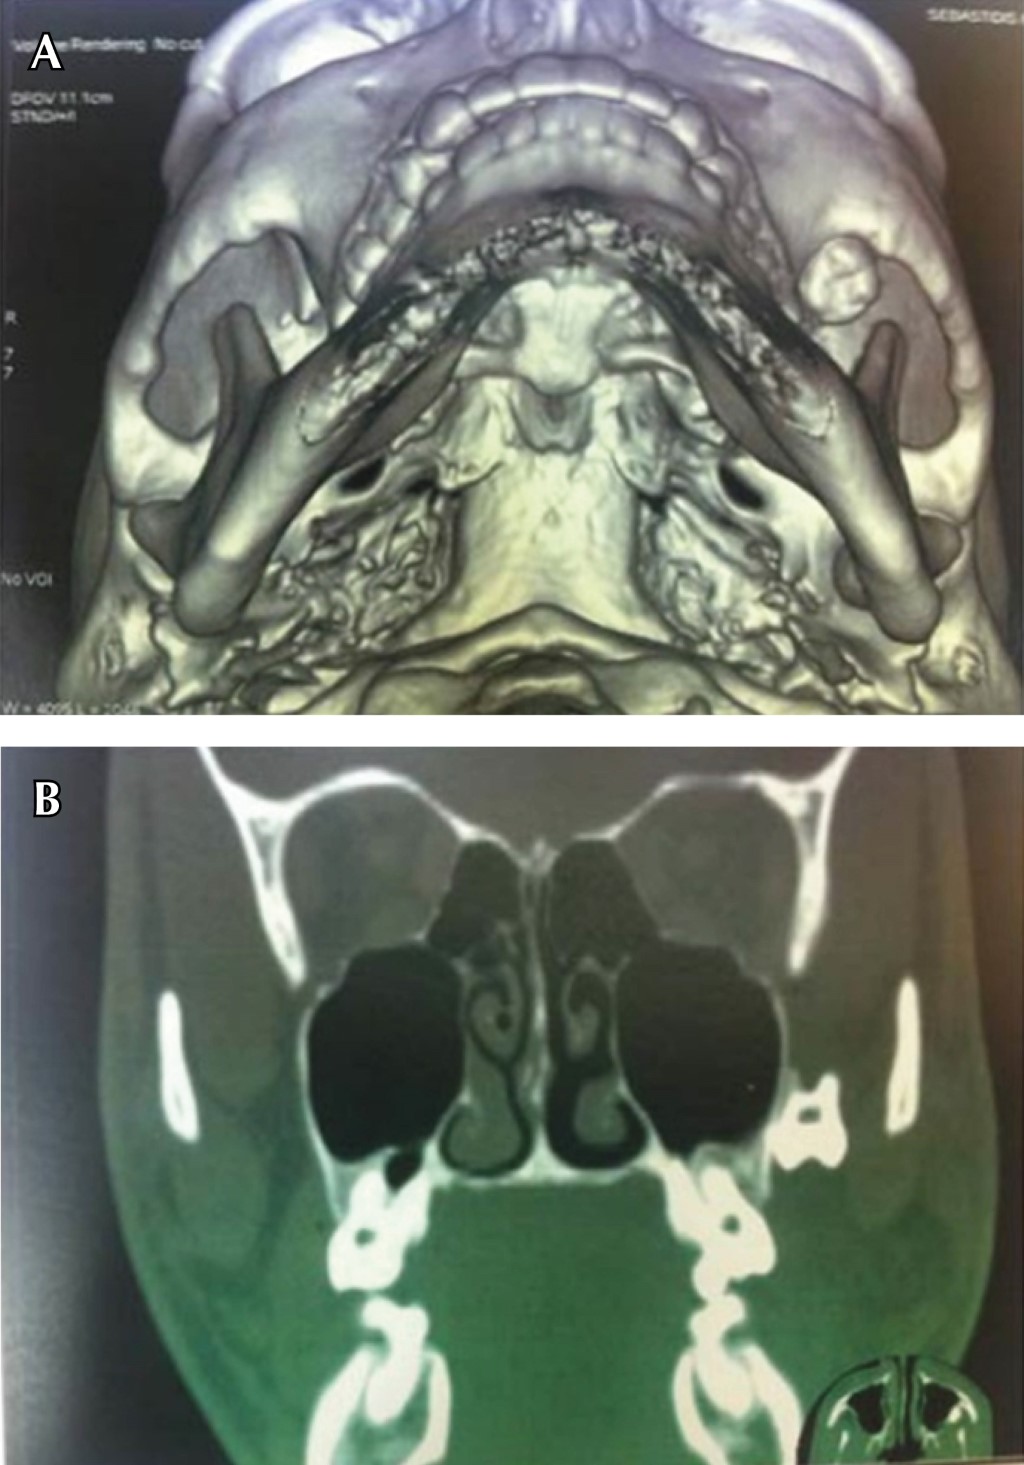

Tal como se refleja en el estudio realizado por Masui M y colaboradores denominado Displacement of lower third molar into floor of mouth: a single institutional experience,8 en el cual desarrollaron un análisis retrospectivo del manejo del tercer molar inferior desplazado hacia el piso de la boca, tomando en cuenta siete pacientes cuyo rango de edades iba de los 20-62 años, entre un periodo de tiempo que abarca del 2010-2020, el cual obtuvo como resultado: seis casos en donde el tercer molar fue desplazado hacia el espacio submandibular y un caso al espacio sublingual. Estas unidades dentarias o fragmentos dentarios, fueron retirados de piso de boca a través de un abordaje intraoral en seis casos, ya que únicamente un caso no se abordó; cuatro casos fueron abordados bajo anestesia general y dos casos bajo anestesia local, al igual que como expresan Tilaveridis I y asociados en el estudio denominado Displacement of maxillary third molar into the infratemporal fossa. A case report9 en donde se reportó el caso de un paciente masculino de 17 años de edad con desplazamiento de tercer molar superior izquierdo, luego de la evaluación de la tomografía computarizada se pudo evidenciar la presencia del tercer molar desplazado en la fosa infratemporal ipsilateral (Figura 1), su intervención fue bajo anestesia general, a través de un abordaje intraoral, en el cual la recuperación de la unidad fue de manera exitosa (Figura 2). De igual manera, Rivas y colegas en su estudio Tercer molar desplazado a fosa pterigomaxilar: reporte de caso5 presentan el caso de un paciente de sexo femenino de 16 años de edad, durante la cirugía de los terceros molares, la unidad 28 fue perdida de vista por parte del operador, indicaron radiografías panorámicas y tomografía de haz helicoidal, después de su evaluación se evidenció la ubicación de la unidad, el cual se encontró en la fosa pterigomaxilar (Figuras 3 y 4). Se realizó un abordaje intraoral bajo anestesia local, hasta alcanzar la unidad dentaria desplazada y recuperarla de manera exitosa.

Figura 3

Figura 4